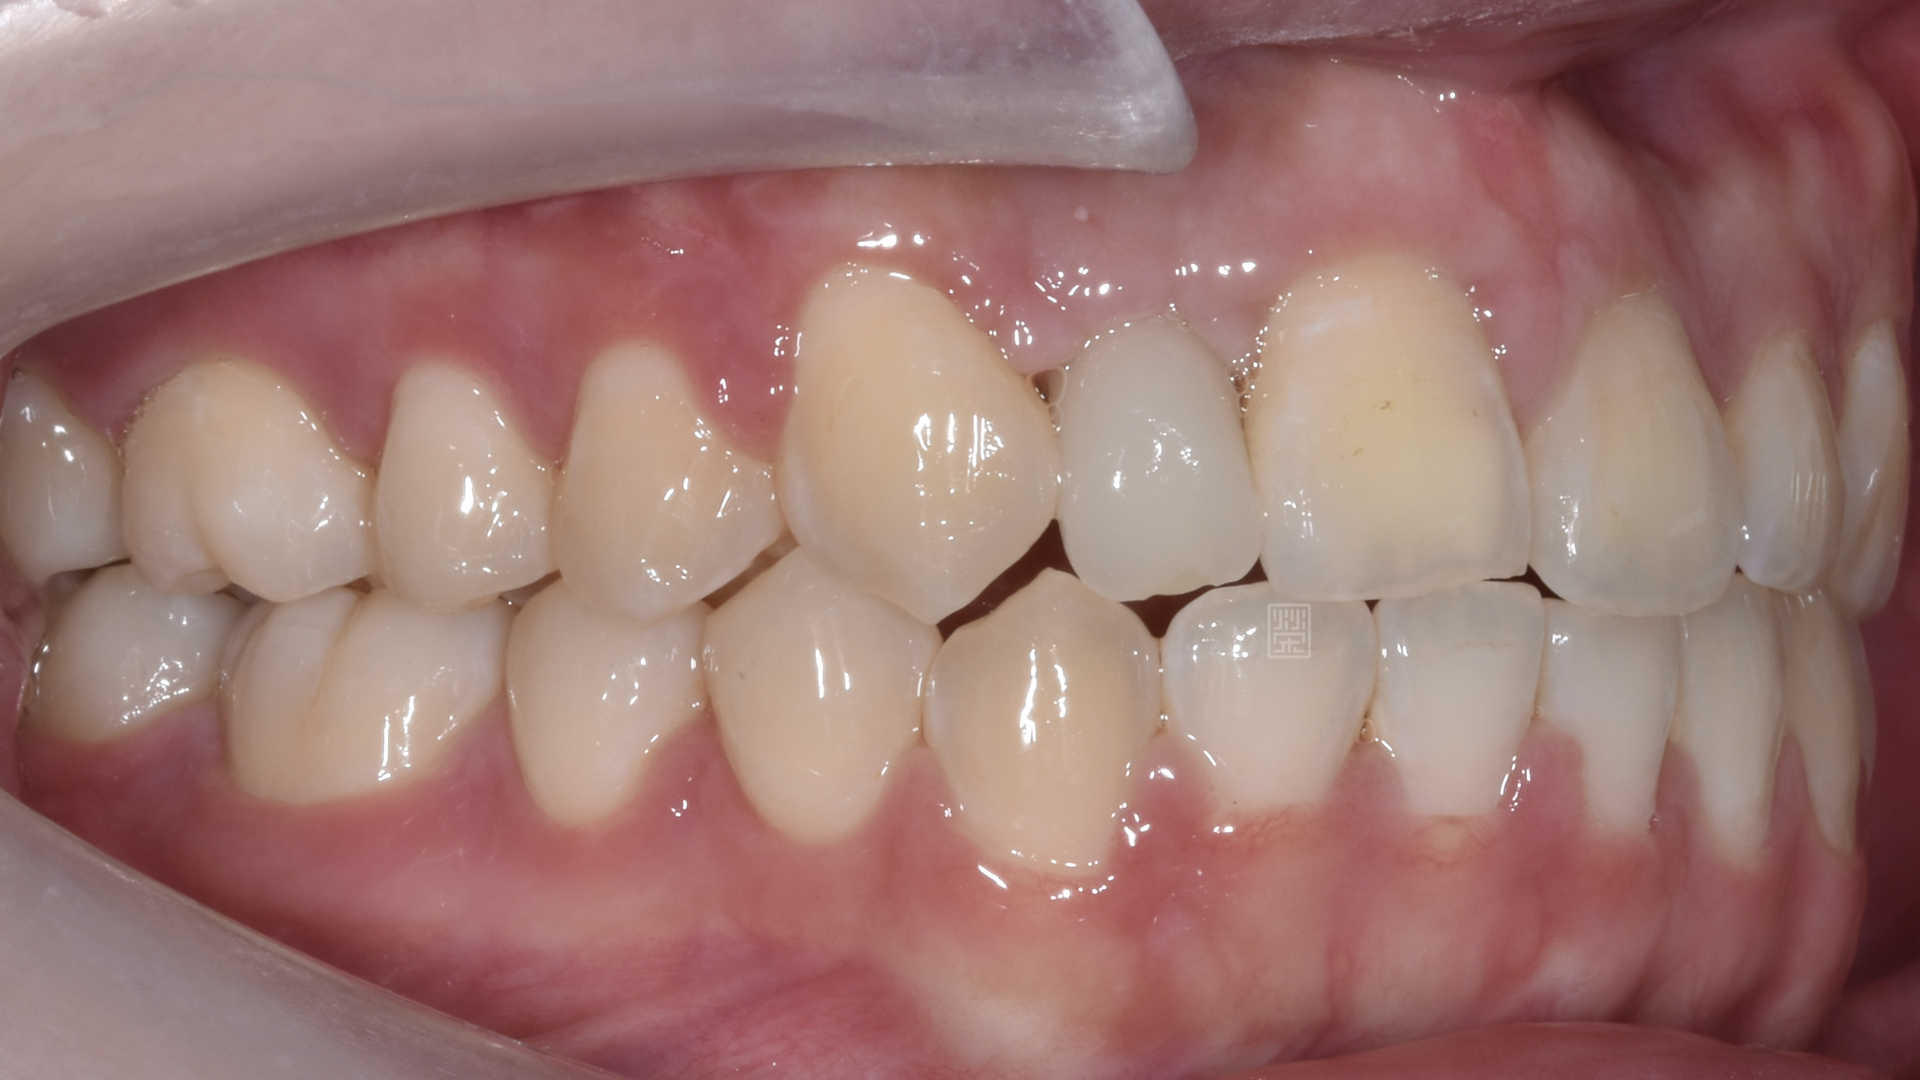

治療前牙齒因車禍有縫且缺牙

長期缺牙側門牙空間不足

姚小姐在國中時因為車禍外傷,造成右側門牙位置撞偏,右側側門牙撞飛,之前也想過處理,諮詢過許多醫師,不是覺得太複雜,就是建議直接牙齒拔除都用植牙來處理。